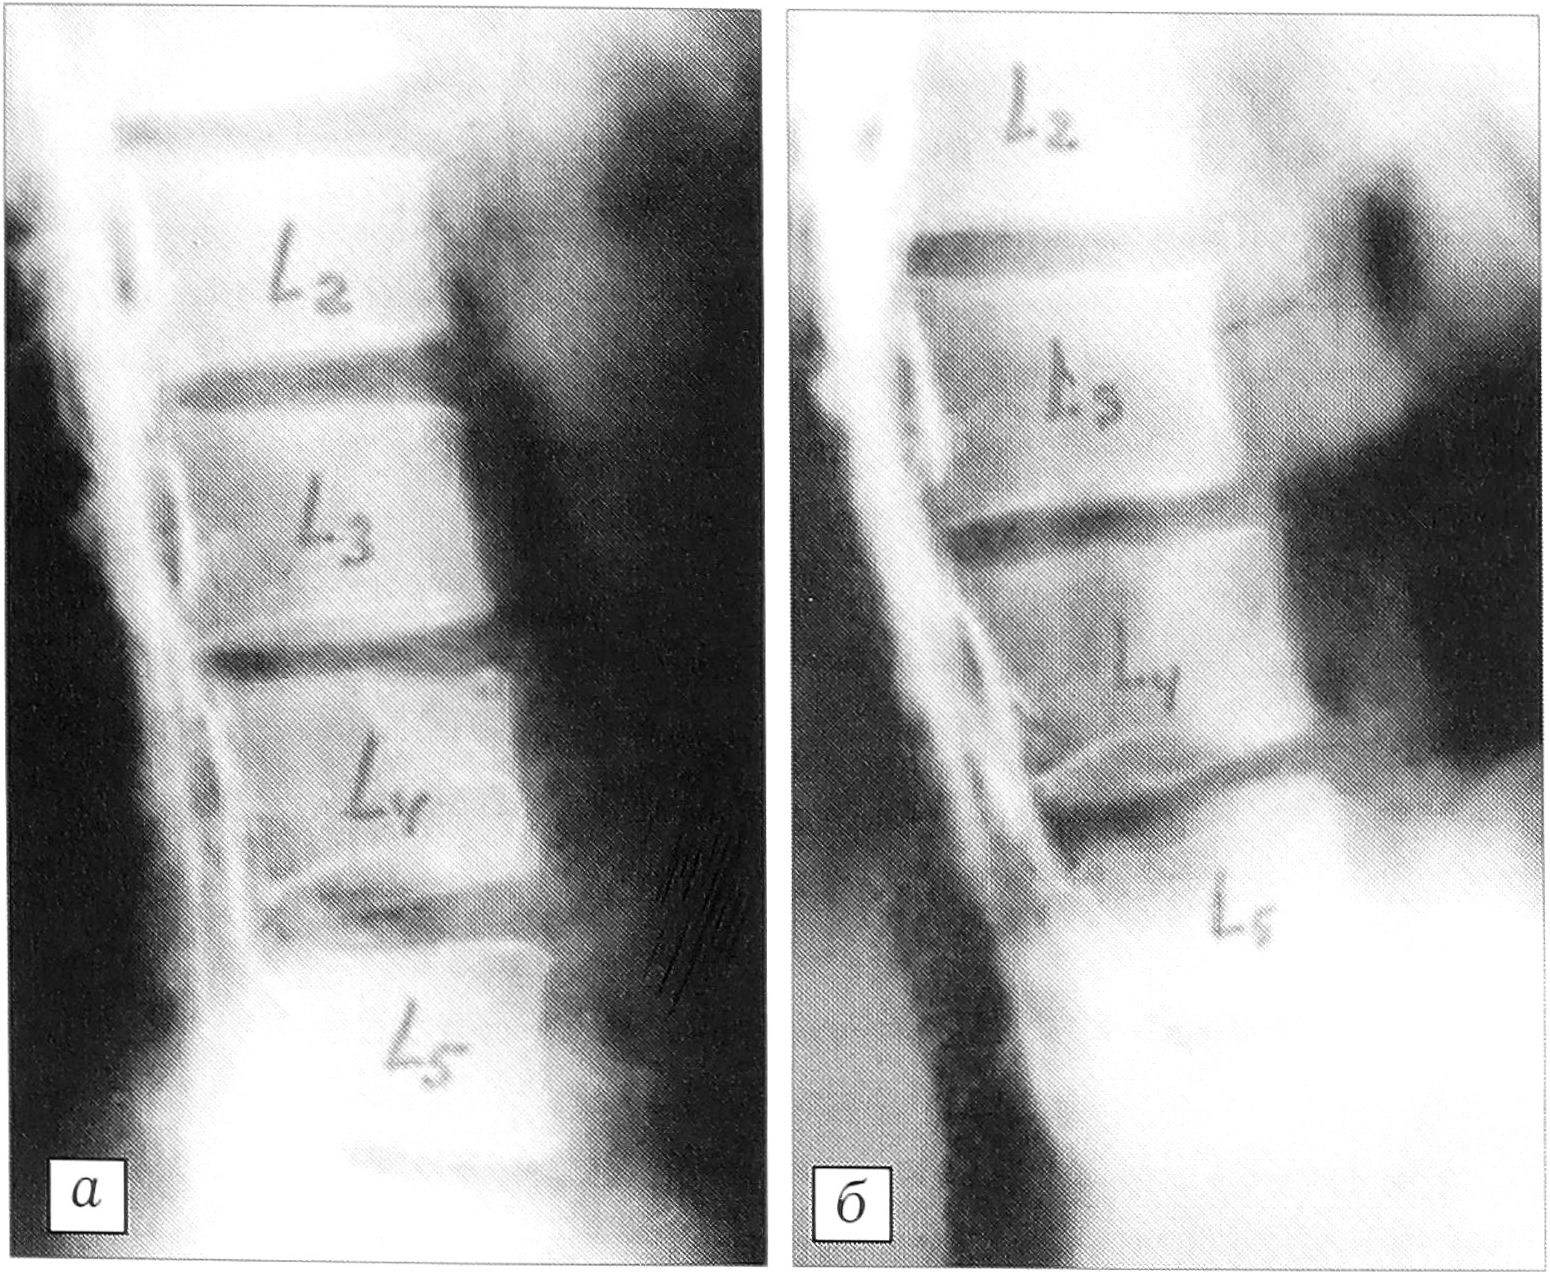

В результате компенсаторного поясничного гиперлордоза формируется передний наклон крестца; чрезмерные нагрузки в межсуставной части дуги нижнепоясничных позвонков приобретают характер дистракции вдоль продольной оси дуги [20], что ведет к истончению и удлинению этого участка позвонка и его возможному стрессовому перелому. В условиях переразгибания нижнепоясничных сегментов вследствие компенсаторного гиперлордоза адаптивная гипертрофия капсульно-связочного аппарата является фактором, противодействующим значительному скользящему смещению позвонка (рис 9, а).

При сглаженности физиологических изгибов позвоночника в области поясничного гиполордоза происходит перегрузка переднего опорного комплекса, что обусловливает адаптивную перестройку в системе «межпозвонковый диск—тело позвонка». Недостаточность компенсаторных возможностей может привести к дезадаптации поясничных сегментов и, в зависимости от пути фактического отказа, к клинической манифестации дискалгического синдрома или синдрома нестабильности. Сопутствующие диспластические изменения переходного пояснично-крестцового позвонка (высокое стояние позвонка, гипоплазия и удлинение дуги, вертикализация крестца, spina bifida) способствуют развитию диспластического элонгационного спондилолиза с последующим скользящим нестабильным смещением позвонка (рис. 9, б).

Рис. 9. Истмический спондилолистез (а) и элонгационный спондилолистез (б) L5 позвонка при остеохондропатии.